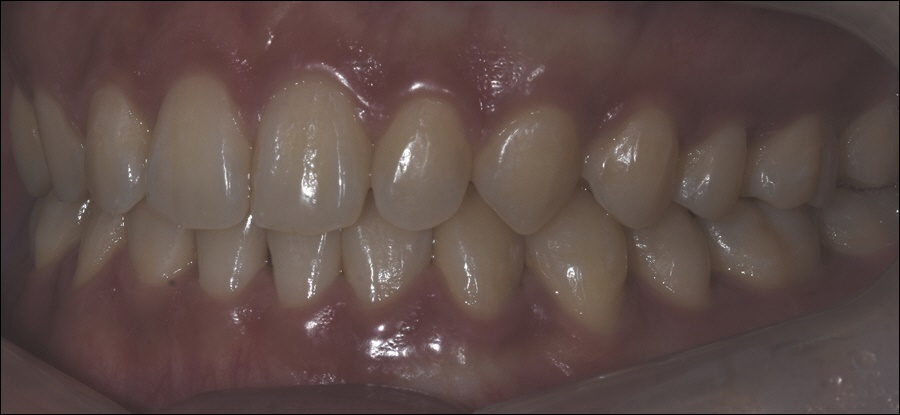

이렇듯 신논현치과에서 진행하고 있는

인비절라인은 투명한 특수 재질의

플라스틱으로 제작되고 있기 때문에

치아 교정을 진행하고 있는 기간에도

심미적으로도 만족스럽게 치아를

가지런하게 이동시킬 수 있었습니다.

더불어 탈착이 가능한 장치이기 때문에

위생 관리에도 용이하였으며, 음식물을

섭취하거나 칫솔질을 할 때, 뺄 수 있었어요.

또한 1:1 맞춤으로 제작되기 때문에

이물감이 적다는 것이 장점으로 꼽히고

있었으며, 발음도 정확하게 구사했어요.